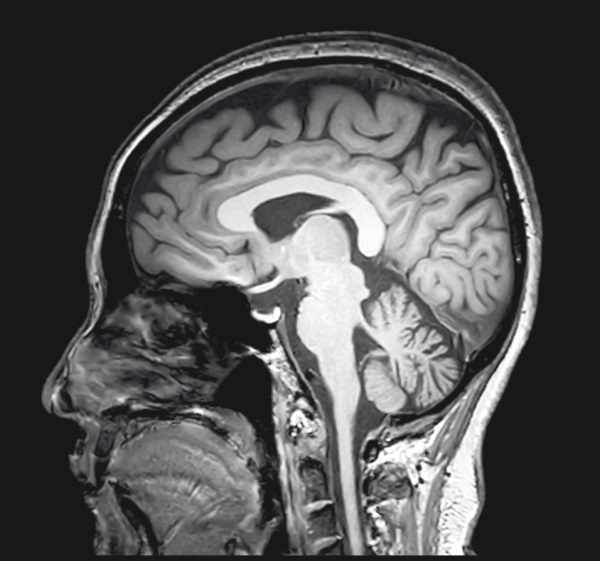

Иллюстрация к книге — Квантовый мир. Невероятная теория в самом сердце мироздания [i_022.jpg]

Рис. 6.2. Принцип работы квантового компьютера сравнивают с принципом работы мозга.